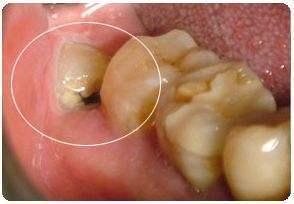

首先,得先弄清楚什么是龋齿。简单来说,龋齿就是牙齿上的小洞洞,通常是由食物残渣、细菌和唾液混合在一起,长时间停留在牙齿表面,导致牙齿被慢慢腐蚀。听起来是不是有点恐怖?其实,这就是我们日常生活中常见的口腔问题。

那么,当龋齿严重到需要拔牙时,这个过程又是怎样的呢?下面,我们就来一起看看成人龋齿拔牙的视频过程图。

现在,让我们来看看一些成人龋齿拔牙的视频过程图,让你更直观地了解这个过程。

这张图展示了拔牙前的准备工作,包括医生检查和注射麻醉。